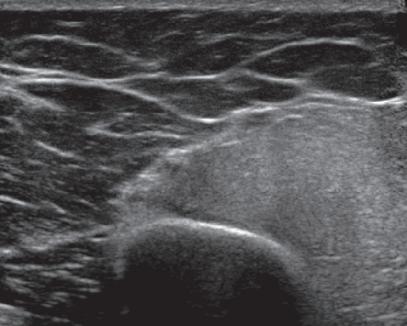

is fusion imaging, in which real-time ultrasound imaging can be superimposed on computed tomography (CT) or MRI; this has been used to assist with needle guidance for sacroiliac joint injections.17 One last technique is sonoelastography, which is used to assess the elastic properties of tissue. The three types of sonoelastography include compression elastography (using manual compression), shear wave elastography (using a directional shear wave), and transient elastography (using a short pulse).18 With compression elastography, manual compression of tissue produces strain or displacement within the tissue. Displacement is less when tissue is hard; it is displayed as blue on the ultrasound image, whereas soft tissue is displayed as red (Fig. 1.27). With regard to musculoskeletal applications, normal tendons appear as blue, whereas areas of tendinopathy, such as of the Achilles tendon or common extensor tendon of the elbow, appear as red.16,19-22 With shear wave and transient elastography, the velocity of the shear wave is measured to determine elasticity and has the advantage of less operator dependence and ability to produce qualitative and quantitative information.18,23

area below white arrow). Note that hard tissues are displayed in blue and soft tissues in red. (Courtesy